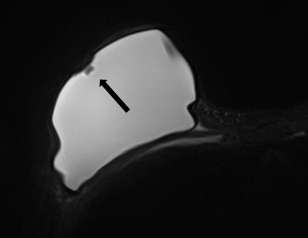

Minimally collapsed intracapsular rupture appears as a hypointense line that runs parallel to the fibrous capsule against the hyperintense extravasated silicone gelon silicone-sensitive MRI images, termed the “subcapsular line sign” (Figure 3).

Axial STIR MRI with arrows demonstrating subcapsular lines of bilateral intracapsular ruptures.

Figure 3: Axial STIR MRI with arrows demonstrating subcapsular lines of bilateral intracapsular ruptures.

Figure 6: Axial T2-weighted image showing a teardrop sign of intracapsular rupture (red arrow) and subscapular line sign (black arrow).